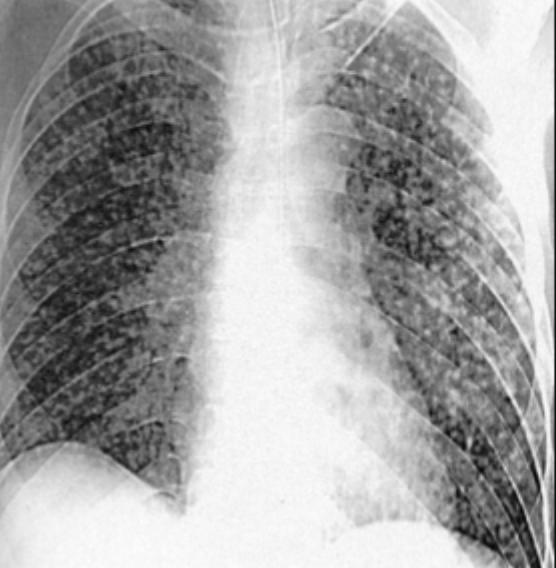

Q

What is this ?

A

Miliary TB

-Lots of little bits of TB in blood showering lung

-Spots also seen in eye and everywhere; probbaly in brain as well